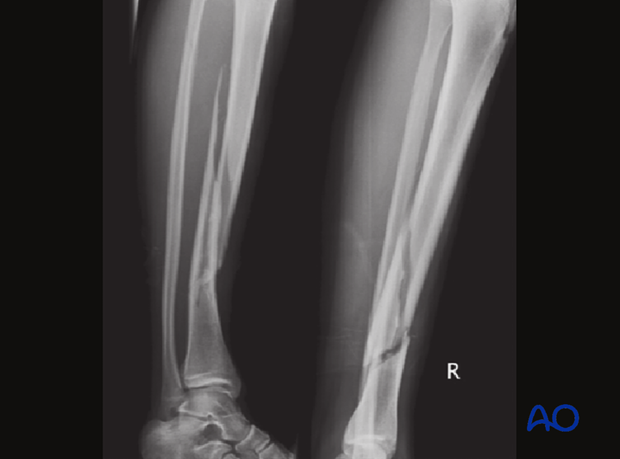

The clinical case shows a 15-year-old girl who sustained a closed comminuted tibial fracture from a skiing injury, AO classification 42C2.

The initial treatment was an open reduction and plate osteosynthesis.